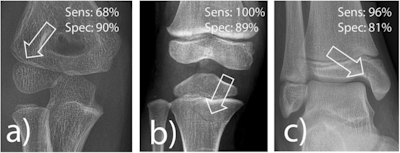

Frequently missed fracture entities with medicolegal significance according to van Laer. a Radial condyle fracture, (b) fracture of the proximal tibia, and (c) fracture of the medial malleolus. The lucency marked by an arrow indicates the fracture. Sens, sensitivity; Spec, specificity.

For the medicolegally relevant cohort, AI attained sensitivity of 100% for proximal tibia fractures, 96% for medial ankle fractures, but only 68% for radial condyle fractures. The latter finding was noted by the authors as cause for concern, as the three fracture types were chosen for their medicolegal significance, and the elbow being a particularly common area for misinterpretation.